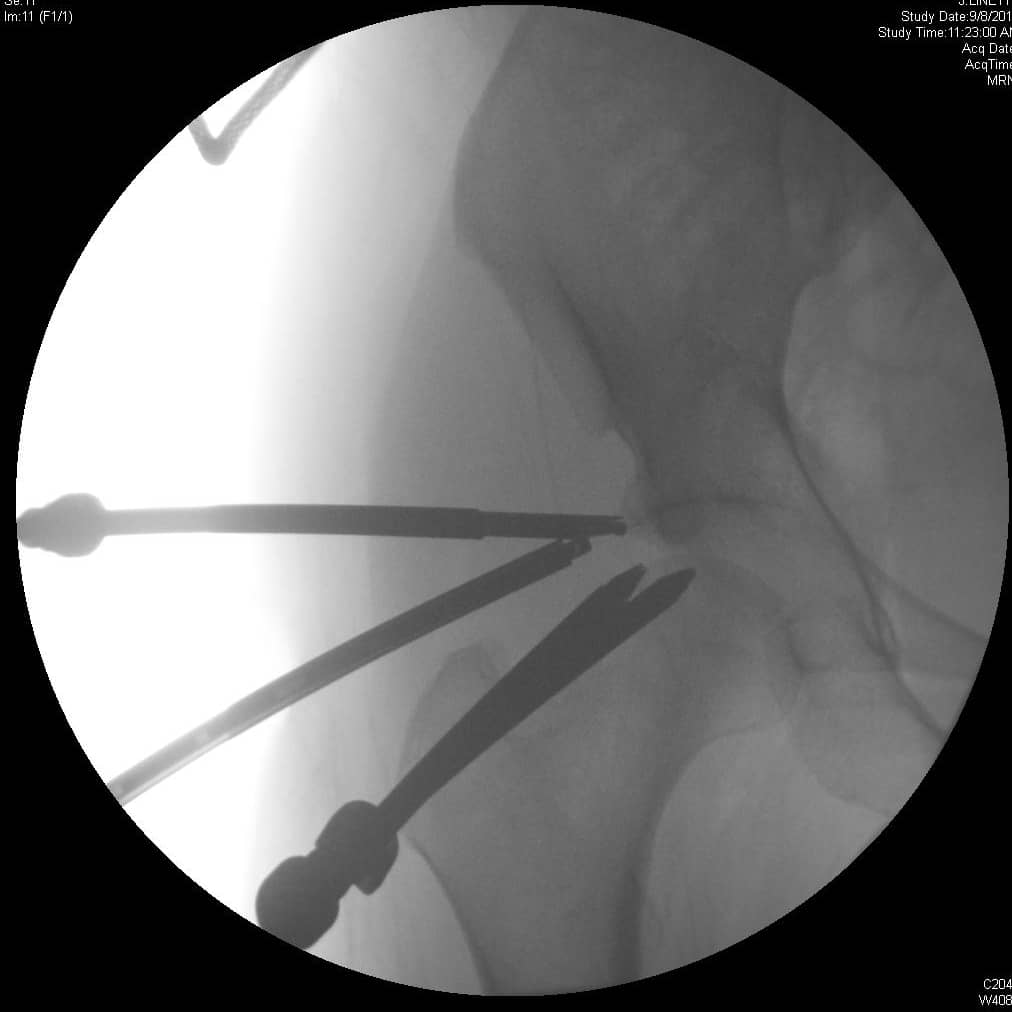

एसिटैबुलर ओस्टियोप्लास्टी और लैब्रल मरम्मत के साथ हिप आर्थ्रोस्कोपी

एफएआई के लिए प्रारंभिक गैर-शल्य चिकित्सा प्रबंधन में गतिविधि संशोधन और विरोधी भड़काऊ दवा शामिल है। शल्य चिकित्सा उपचार की प्रगति उन रोगियों के लिए विचार की जानी चाहिए जो रूढ़िवादी प्रबंधन में विफल होते हैं। ऊरु गर्दन के घावों या लैब्रल आंसुओं के सर्जिकल उपचार का इलाज खुले या आर्थोस्कोपिक डिब्राइडेशन और लैब्रल मरम्मत या शोधन द्वारा किया जा सकता है। खुले उपचार के संकेतों में गैर-गोलाकार ऊरु सिर, सिर-गर्दन ऑफसेट में कमी, पिंसर का टकराव, और पीछे के कूल्हे के घाव शामिल हैं। बर्नीज़ पेरियासेटाबुलर ओस्टियोटॉमी एक खुली एसिटेबुलर रीओरिएंटेशन प्रक्रिया है जिसका लक्ष्य एसिटेबुलर रेट्रोवर्जन को कम करना है। एसिटाबुलम की चोंड्रल चोटों का इलाज चोंड्रोप्लास्टी, ड्रिलिंग या माइक्रोफ्रैक्चर द्वारा किया जा सकता है, जिसका उद्देश्य फाइब्रोकार्टिलेज रीग्रोथ को प्रोत्साहित करना है। एसिटेबुलर एंटीवर्सन और पश्चवर्ती ओस्टियोफाइट के प्रभाव का इलाज एसिटाबुलम के रिम एक्सिशन के साथ किया जा सकता है। आर्थोस्कोपिक नैदानिक परिणाम एफएआई के उपचार के लिए खुले सर्जिकल नैदानिक परिणामों के समान दिखाई देते हैं। 2, 3

एफएआई के लिए सर्जिकल मरम्मत पर्याप्त संयुक्त स्थान वापस करने का प्रयास करती है ताकि एसिटाबुलम के खिलाफ ऊरु सिर या गर्दन के झुकाव के बिना कूल्हे की गति की अनुमति मिल सके। इस स्थान को कम करने वाले घावों का छांटना अपक्षयी प्रक्रिया को संभावित रूप से धीमा करने और दर्द और अन्य लक्षणों को हल करने के लिए किया जाता है। आर्थ्रोस्कोपी समान नैदानिक परिणामों के साथ पारंपरिक खुली सर्जरी के लिए एक कम-आक्रामक विकल्प प्रदान करता है। 4, 7

रोगियों को पता होना चाहिए कि प्रक्रिया के समय चोंड्रल क्षति की डिग्री अपेक्षित परिणाम से संबंधित है। पुराने रोगियों और हस्तक्षेप के समय अपेक्षाकृत कम संयुक्त स्थान वाले लोगों को बाद में कुल हिप प्रतिस्थापन की आवश्यकता होने की अधिक संभावना है। 2 मिमी ≥ वाले रोगियों में बढ़ी हुई संतुष्टि देखी जाती है और क्षतिग्रस्त लैब्रम की मरम्मत के साथ इलाज किया जाता है। 8 इसलिए, एक सापेक्ष मतभेद गंभीर संयुक्त स्थान संकुचित (< 2 मिमी) है। ऊरु सिर की चोंड्रल क्षति उन्नत बीमारी को इंगित करती है और बदतर परिणामों से जुड़ी होती है। एफएआई के आर्थोस्कोपिक मरम्मत के कई पहलुओं से जटिलताएं हो सकती हैं। बेहतर ग्लूटियल या फेमोरल न्यूरोवास्कुलर बंडलों या पार्श्व ऊरु त्वचीय तंत्रिका के निकटता में पोर्टल प्लेसमेंट प्रक्रिया के दौरान इन संरचनाओं को जोखिम में डाल सकता है। प्रक्रिया के दौरान कर्षण से साइटिक तंत्रिका की चोट हो सकती है, जिसे कर्षण के कोमल अनुप्रयोग के साथ कम किया जा सकता है। एवैस्कुलर नेक्रोसिस का खतरा ऊरु गर्दन के 30% से अधिक शोधन के साथ बढ़ता है। सभी एक्सिशन प्रक्रियाओं के साथ, फ्रैक्चर अतिरिक्त हड्डी को हटाने के परिणामस्वरूप हो सकता है। 4